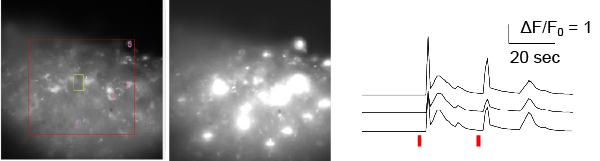

Brain activity is regulated by neuromodulators such as adenosine, dopamine, serotonin, and noradrenaline. Increases or decreases in these modulators are thought to underlie psychiatric disorders such as depression and schizophrenia. Therefore, we analyzed neuromodulators during mouse depression-like behavior, which works as a model for understanding human motivation. Our research has revealed that the water channel (AQP4) in astrocytes, a type of glial cell, regulates the levels of adenosine and dopamine, and that abnormalities in this process cause depressive-like behavior. In this research, we created sensor cells that increase fluoresce in response to adenosine or dopamine using genetic engineering, placed brain slices on top of these cells, and measured dopamine release in response to electrical stimulation and adenosine release in response to hypoosmolality (Figure a). Cocaine, a type of stimulant drug, can cause depression as a withdrawal symptom, so we made brain slices from mice that had been administered cocaine and used them in the measurements. We found that, in association with depressive-like behavior, AQP4-dependent adenosine release increased, and that this adenosine suppressed dopamine neurotransmission (Figure b). In fact, AQP4-deficient mice do not show depressive-like behavior induced by cocaine. Currently, we are conducting research using two-photon holographic microscopy, focusing on points such as “how does cocaine administration affect brain activity?” and “does this effect change in AQP4-deficient mice?”.